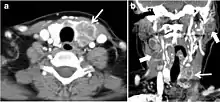

Metastasis to the thyroid

Metastasis to the thyroid is rare and represents 5.5% of biopsied thyroid malignancies. It is commonly found with cancers originating from the breast, renal cell, lung, melanoma, and colon. Direct invasion from adjacent structures such as the pharynx, larynx, trachea, or oesophagus has been reported (Fig. 10). Metastatic disease has a non-specific appearance.[1]

Fig. 10. Metastatic squamous cell carcinoma of unknown origin in a 42-year-old female patient. a, b Axial and coronal enhanced neck CT scan demonstrate infiltrative hypodense left thyroid lobe lesions (white arrows). There are multiple necrotic cervical nodal metastases (white block arrows).[1]

The presence of ITNs in patients with another known malignancy is a common clinical problem with controversial management guidelines. Wilhelm et al. followed 41 patients with a known extra-thyroid malignancy and ITNs; 35 of them met the criterion for biopsy (nodule ≥ 1 cm). Pathology revealed four papillary thyroid cancers and five micropapillary thyroid cancers. Only two metastatic cancers were detected. Clinical history (history of radiation, age, endocrine syndromes), TSH, nodule size, and sonographic features are important to determine which nodule(s) should be followed or biopsied. However, existing guidelines do not specifically address how to approach ITNs detected on CT scans in such a specific patient population.[1]